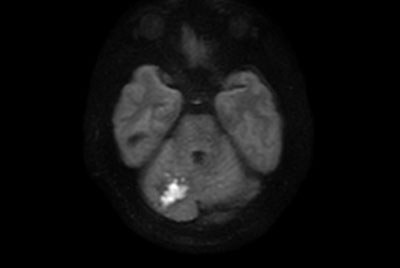

Brain infarction